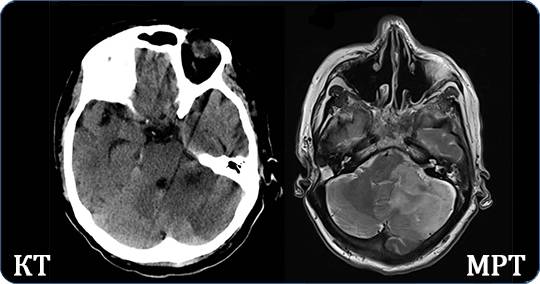

- В компьютерной томографии (КТ) и в рентгене используются рентгеновские лучи. Они позволяют оценить размер, положение, плотность органа, тканей и выявить патологию путем сопоставления с нормальными значениями здоровых объектов. Отличие КТ от рентгена состоит в том, что аппарат многократно сканирует исследуемую область. Доктор получает изображения с высоким разрешением в трех проекциях без теней от наложения органов. Информация касается анатомического строения органов, их физических показателей.

- Чем отличается МРТ от рентгена? МРТ использует магнитное поле для создания детальных изображений органов и тканей тела. То есть магнитно-резонансный томограф вызывает отклик молекул воды нашего организма и использует это для создания трехмерных изображений. Техника анализирует строение тканей, дает максимально возможную точность диагностики заболеваний головного, спинного мозга, онкологии разной локализации.

- КТ незаменима при обследовании костей, тканей, сосудов головы, чрезвычайно информативна в диагностике туберкулеза и пневмонии, исследовании желудка, кишечника, других полых органов. Метод используется при обследовании позвоночника, костей, однако он не дает полной информации при обследовании суставов, связок, мягких тканей.

- С помощью МРТ диагностируют новообразования, опухоли, обследуют оболочку, ткани головного, спинного мозга. Диагностика инсульта в первые часы помогает врачам быстро принять нужные меры.Огромное значение метод имеет для выявления рассеянного склероза, заболеваний матки, мочевого пузыря, прямой кишки, предстательной железы, онкологии (развитие, локализация новообразования, степень повреждения соседних тканей).